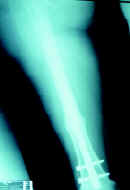

Caso clínico No 3. Paciente de 18 años, con fractura expuesta grado I del tercio medio del fémur manejado con clavo bloqueado; consolidación a las 30 semanas.